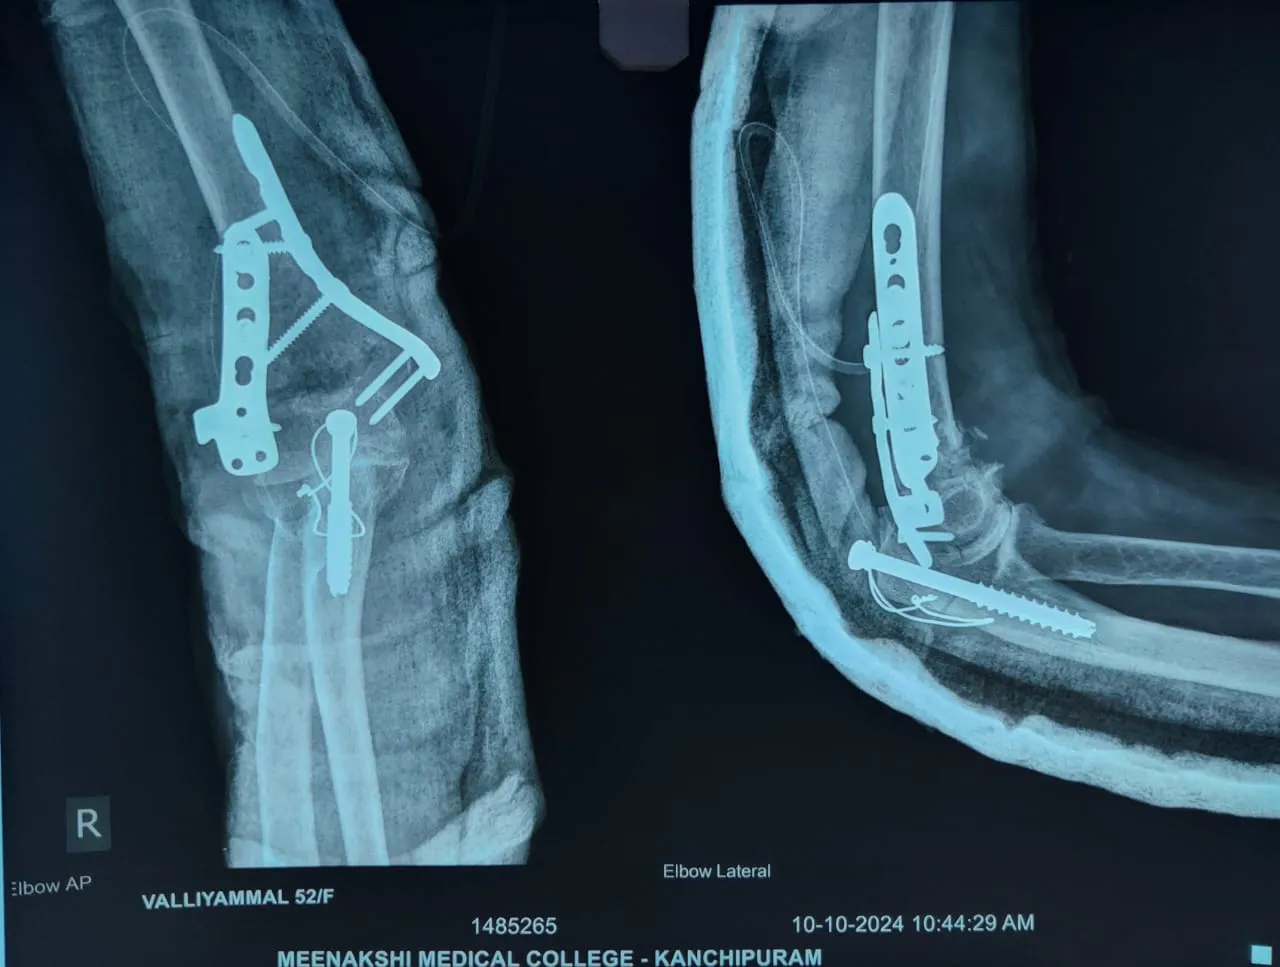

Dr.P.Sankaralingam M.S(ortho)., DNB (ortho).,MNAMS is an experienced senior consultant Orthopaedic surgeon who does about 350 joint replacement surgeries per year in addition to treatment of Trauma cases.

• All Trauma & Fracture Fixation (Nails, Plates, Non-union Repairs)

Accomplishment